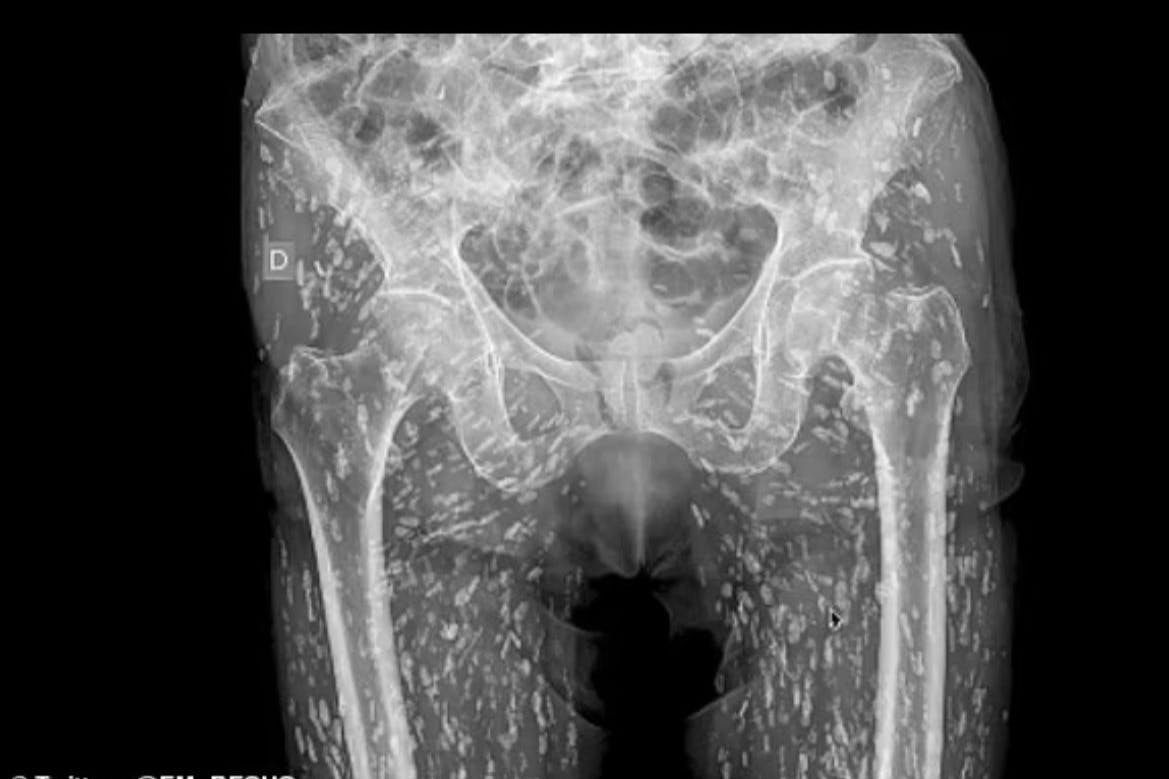

Achtung: Akuter Ekel-Alarm! Das Röntgenbild eines Mannes aus Florida schockt sogar die Mediziner. Denn die Reiskörner-ähnlichen weißen Stellen sind von Bandwurm-Larven erzeugte Mini-Zysten. Diese waren in den Körper des Patienten gelangt, weil dieser nicht ausreichend gekochtes Schweinefleisch gegessen hatte.

Der Notarzt Dr. Sam Ghali hatte das Röntgenbild auf sein X-Konto gestellt, als Warnung für andere, „unter keinen Umständen Schweinefleisch zu essen, das roh oder nicht richtig durchgebraten ist“. Das Verrückte: Der Patient wusste gar nicht, was für eine Horrorshow sich in seinem Körper abspielte – weil er noch nichts davon spürte. Die im Schweinefleisch enthaltenen Bandwurm-Larven hatten sich zu Tausenden in seinem Gewebe rund um den Bauchraum und den Beinen eingenistet, wodurch dann die entzündeten Zysten entstanden.

Der Mann war nur in der Notaufnahme von Dr. Ghalis Krankenhaus gelandet, weil er nach einem Sturz starke Schmerzen im Becken- und Oberschenkelbereich spürte. Der Mediziner klang auf seinem zum Bild begleitenden Video geschockt: „Die Zysten sind überall, man kann sie gar nicht zählen. Das Problem ist, dass sie durch den ganzen Körper wanden können.“ Und das kann lebensgefährlich werden, wenn die geschlüpften Bandwürmer im Gehirn, Nervensystem oder den Organen schwere Infektionen auslösen.